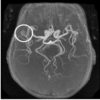

26

right MCA aneurysm

Describe the indication of MRA head/neck

Uses inversion recovery sequences and "time of flight" sequences to differentiate fast moving blood from static surrounding tissues - gadolinium not required **- can identify vascular cut offs, aneurysms, arteriovenous malformation, arterial dissection** (CTA more sensitive for neck vessel dissection)